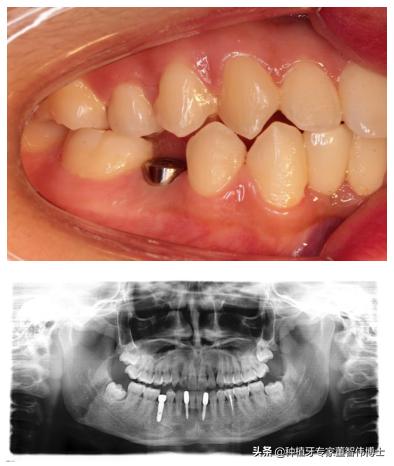

术前,45牙残根 颊侧肉芽组织覆盖

术中,植入1颗种植体颊面观,给与愈合基台覆盖

种植体术后3月颊面观可见种植体愈合良好,X线片可见,种植体位置、角度、深度控制良好